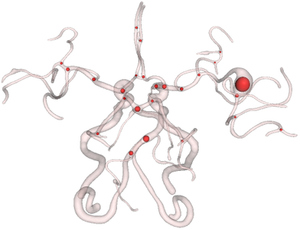

An Insight Toolkit (ITK) processing framework for simultaneous segmentation of multiple objects using active contours without edges is presented in this paper. These techniques are also popularly referred to as multiphase methods. Earlier, we had an implemented the Chan and Vese [1] algorithm that uses level- sets to accomplish region segmentation in images with poor or no gradient information. The current work extends that submission to use multiple level sets that evolve concurrently. The basic idea is to partion the image into several sets of piecewise constant intensity regions. This work is in contrast to the level-set methods currently available in ITK which necessarily require gradient information and also necessarily segment a single object-of-interest. Similar to those methods, the methods presented in this paper are also made efficient using a sparse implementation strategy that solves the contour evolution PDE at the level-set boundary. This work does not introduce any new filter but extends the earlier submitted to filters to process multiple objects. We include 2D/3D example code, parameter settings and show the results generated on a 2D cardiac image.